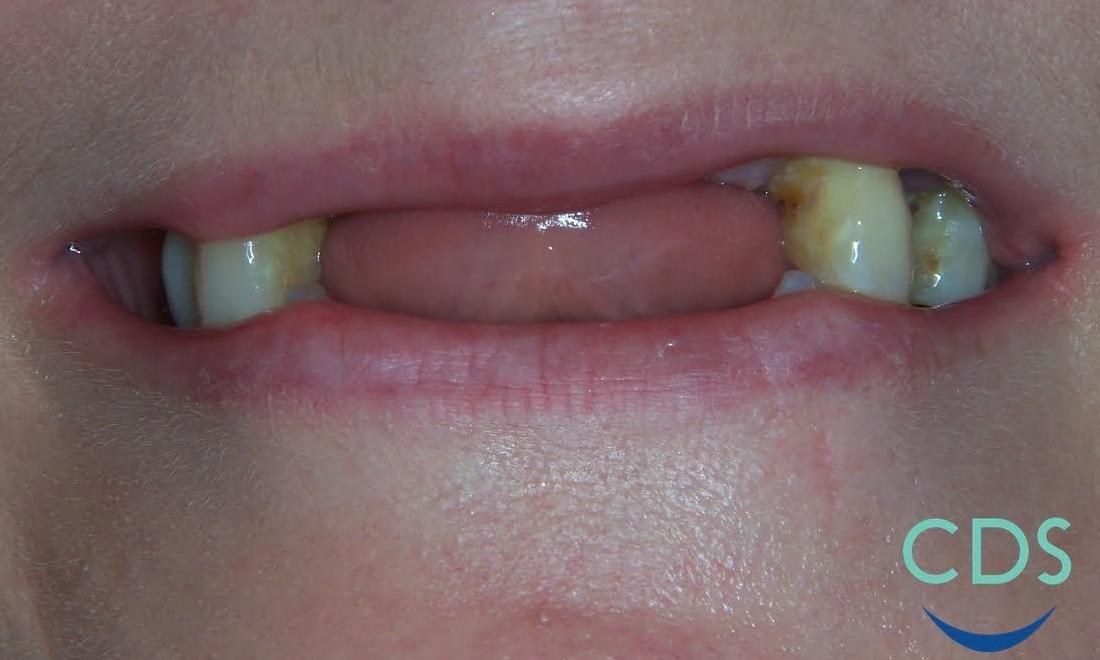

This patient came in will ill-fitting partials and was interested in having the remaining teeth removed to achieve better aesthetics. Because of work, she did not want to go without teeth, so we extracted her remaining teeth and placed her in dentures the same day. Typically, this isn't done to allow for proper healing, but the patient eventually had these relined for a more comfortable fit. We had an excellent outcome in this case and the patient was very happy!